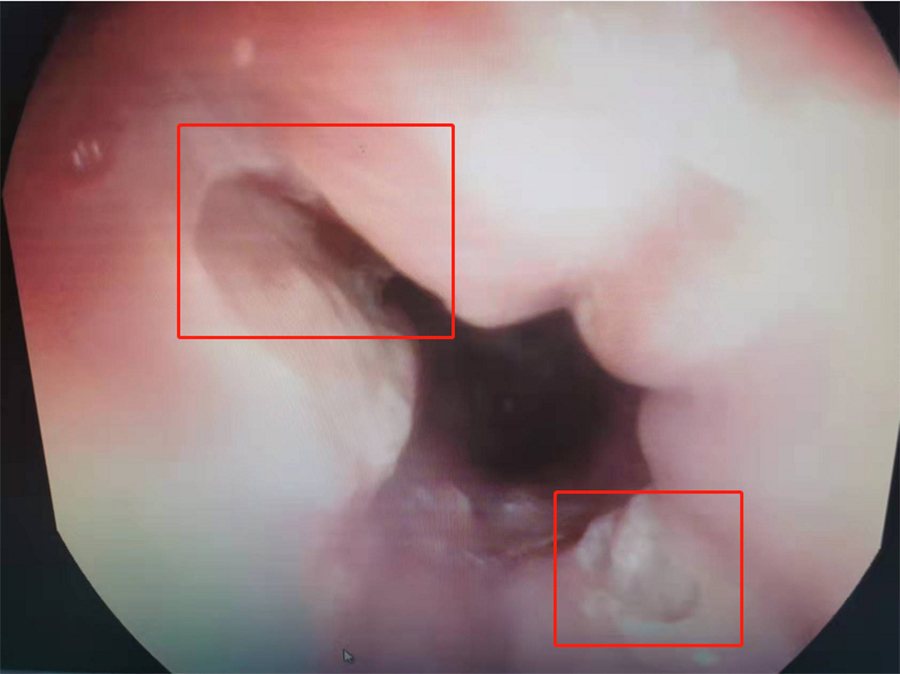

食道下段有两处溃疡

在内镜中心,副主任边鹏为桐桐查体,没发现其上腹胃部区域有压痛。鉴于桐桐腹痛多日,边鹏建议:做胃镜,以明确病因。当胃镜探头进入桐桐食道后,边鹏发现食道下段有两处大面积溃疡,最大处面积达0.3*0.4mm。

溃疡可能是异物所致

临床上,食道溃疡病因很多,常见卡异物后食道损伤,化学性食道损伤、烫伤,部分炎症性肠病也会合并食道溃疡性改变。边鹏根据桐桐食道溃疡对称分布情况,高度怀疑其是误吞异物后造成食道损伤,并有针对性地给出进一步治疗方案:针对食道溃疡,给予口服药物消炎治疗,促进黏膜修复,过一段时间再入院复查。